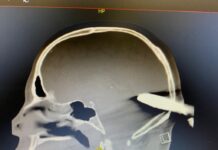

¡De no creer!, esta es la radiografía del taxista al que le clavaron una...

En redes sociales circula la radiografía del taxista al que uno de sus colegas le enterró una cruceta en medio de una riña que se registró en la Terminal del Norte, en Medellín.